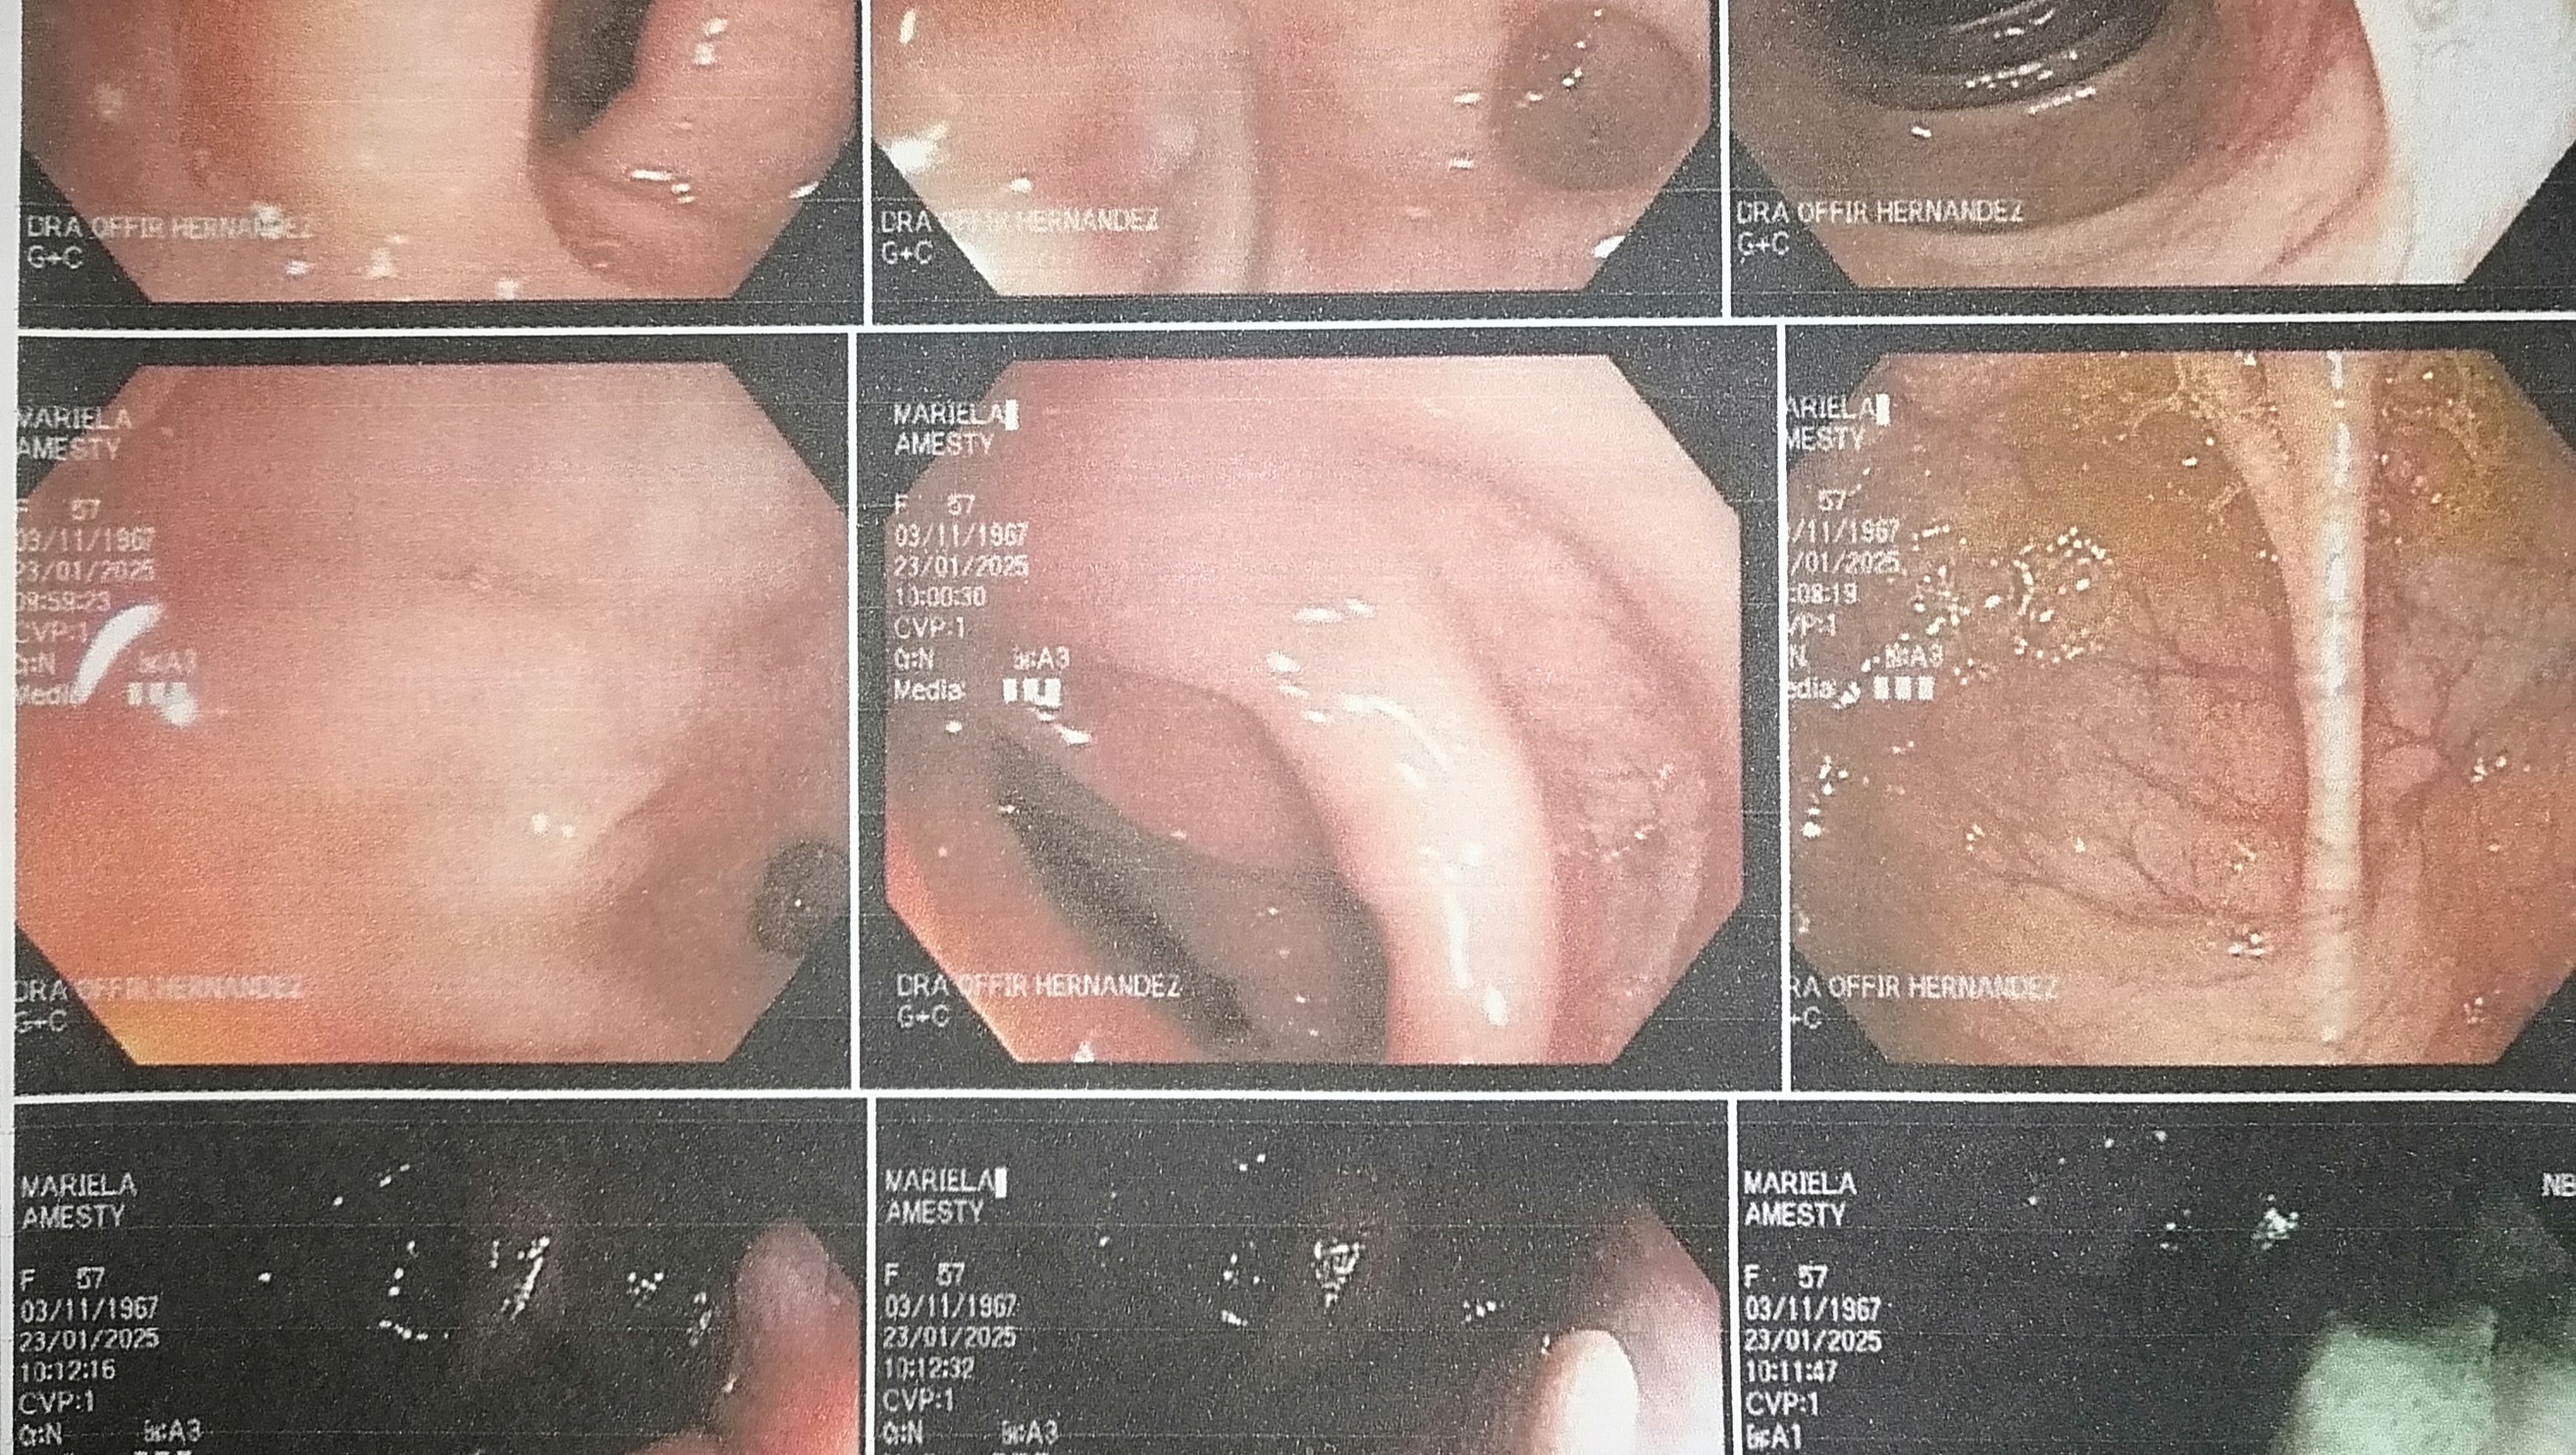

Hola, me llamo Mariela, despues de realizarme una GASTROCOLONOSCOPIA por malestares fuertes, me realizaron dos tomas de biopsia y por los resultados fui redirigida a otro especialista, asisti a consulta Medica con el Proctologo recomendado, quien despues de los examenes que solito me realizó una toma de Biopsia a la lesión anal qué se visualizo en anteriores estudios médicos, la cual arrojó CONDILOMATOSIS con patologías de alto riesgo por lo cual debo ser intervenida quirúrgicamente con urgencia para remover dicha lesión a nivel Anal.

Como tercer plano les dejo otros de los diagnósticos qué arrojó la GASTROCOLONOSCOPIA

-GASTROPATIA NODULAR, CORPORAL Y FUNDICA

-HERNIA HIATAL

-ÚLCERA DUODENAL

-TETS + PARA HELICOBACTER

-ENFERMEDAD DIVERTUCULAR EN EL COLON

-LESIONES PROTUYENTES DE CANAL ANAL